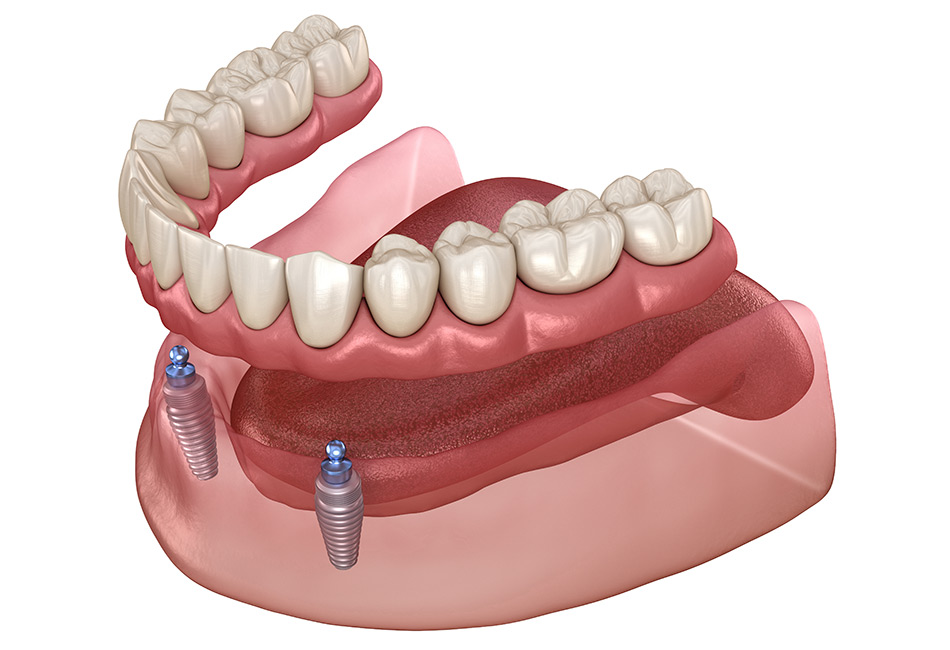

The Dental Implant Procedure

Placement of the Implant

If you’re a good candidate for dental implants near you, we’ll proceed with placing the dental implant. This involves a minor surgical procedure in which a titanium post is inserted into your jawbone. We use local anesthesia to ensure you’re comfortable throughout the process. Over time, the implant will fuse with the bone in a process called osseointegration, which typically takes a few months.

Attaching the Abutment

Once the implant has joined with the bone, a small piece called an abutment is attached. This abutment connects the implant to the new tooth. It sits above the gums and may need a small procedure to put it in place.

Fitting the Artificial Tooth

After the abutment is ready and your gums have healed, we’ll take a mould of your mouth to make a custom tooth (crown) that fits just right. The crown is then attached to the abutment, completing your dental implant.

1. What are dental implants?

Dental implants are titanium posts surgically placed into the jawbone to replace missing teeth. They act as artificial tooth roots and provide a stable base for attaching crowns, bridges, or dentures.